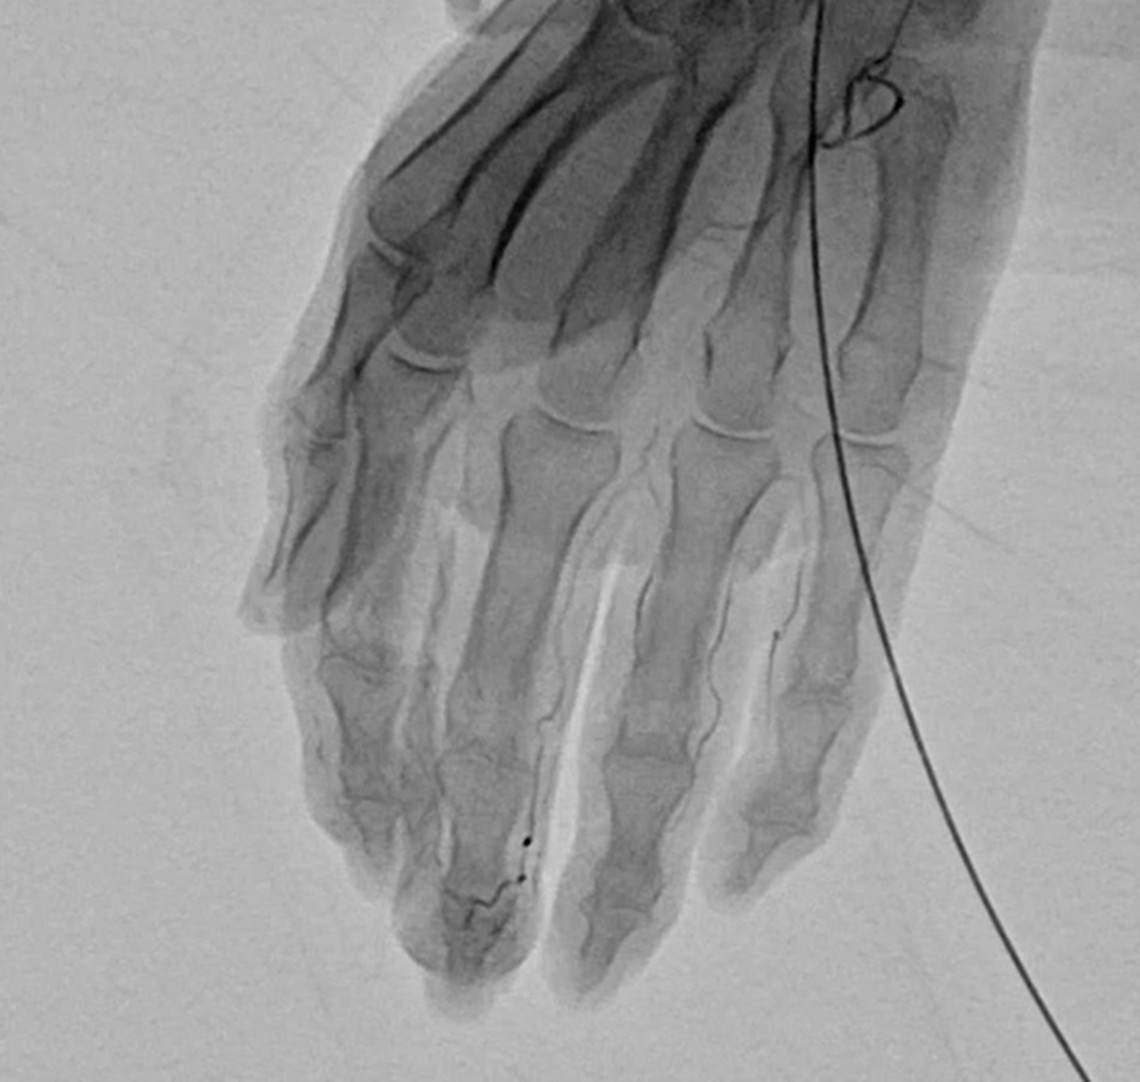

慢性的な痛みが続く部位には、異常な毛細血管(新生血管)=「モヤモヤ血管」が発生していることがあります。これは炎症や組織のダメージにより、けがや炎症が起きた場所の組織を修復しようとして、本来はないはずの場所に過剰に増えてしまった毛細血管です。画像検査で霧がかかったように見えることから「モヤモヤ血管」と呼ばれます。

モヤモヤ血管は、痛みを感じる神経(知覚神経)を巻き込むように増殖します。炎症が治まっても、モヤモヤ血管が神経を刺激し続けることで、慢性的な痛みが続く原因となります。

血管の中に特殊な薬剤を注射して、異常な血管を塞いだり、消滅させることによって、痛みの根本的な治療をはかります。

細い針もしくは留置針をエコーで確認しながら動脈に挿入していきます。